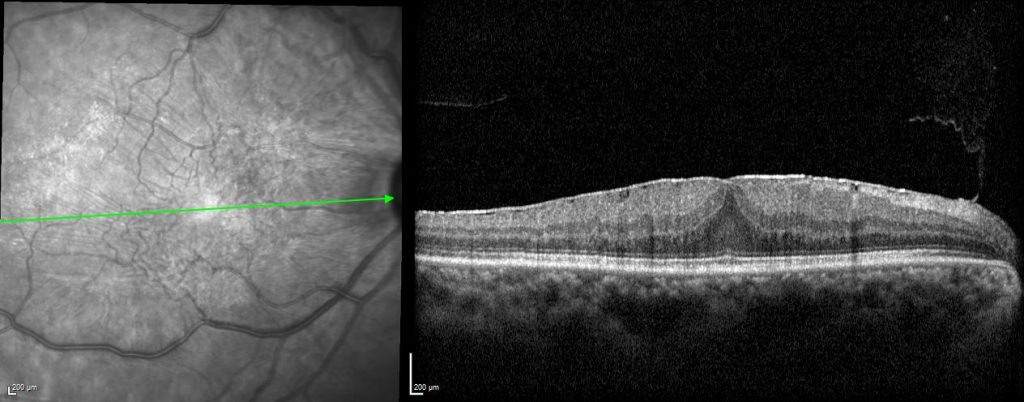

Epiretinal Membrane

An epiretinal membrane (ERM) refers to the development of a thin sheet of tissue or a thin film developing over the central area of the retina called the macula.